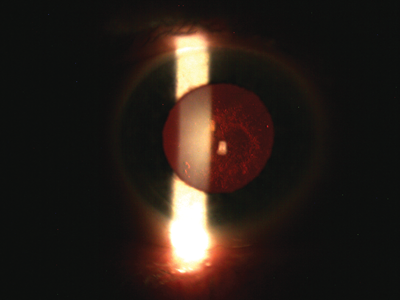

Figure 3: Slitlamp photograph of the culprit responsible for the ‘suddenly’ reduced vision.

However, on examination, to my and the patient’s surprise, the retina was attached circumferentially so that, in the end, the culprit for her symptoms was found to sit more anteriorly as can be seen in Figure 3 and I murmured to myself: “You did it again to me”. It was only a few weeks before that another lady who similarly presented with sudden visual loss and additional temporal pain had nothing but a posterior subcapsular lens opacity (PSCLO) in the end accounting for it.

Nearly every vitrectomised eye develops a subsequent cataract but in most cases this tends to be a nuclear sclerosis rather than a PSCLO [1]. Rahman and colleagues [2] describe another interesting case of sudden onset unilateral nasal hemianopsia respecting the vertical midline on formal testing that was found to be secondary to a posterior subcapsular cataract (which, of interest, was not limited to the temporal aspect of the lens capsule as one might expect). A possible explanation for why PSCLOs appear to be able to mimic other ocular and neurological conditions is put forward by Shun-Shin et al. [3]. They argue that PSCLOs are in a state of flux and are not, as one might assume, slowly but relentlessly progressive, which may also imply the existence of a repair mechanism in the lens.